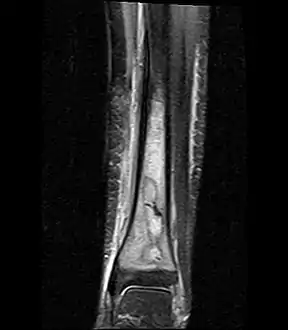

| a,b) MRI showing the Brodie's abscess in the left proximal femur | |

Coronal fat suppressed STIR image showing, bone marrow and subcutaneous edema as well as subperiosteal edema. The thin hypointense rim surrounding the intramedullary collection represents the reactive interface between the abscess and the body's attempt to wall it off.